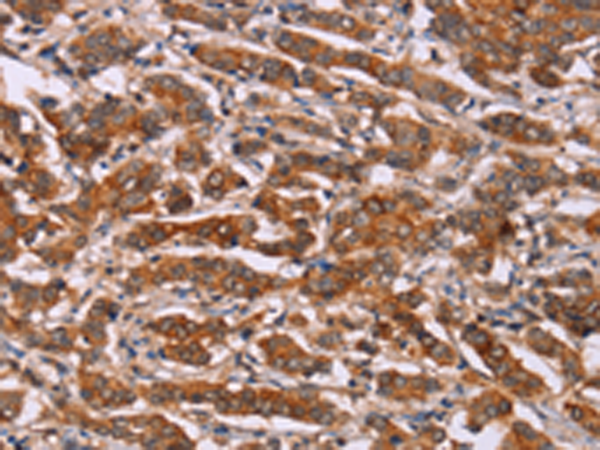

分类: 科研抗体货号: P08197别名: FHI; CPN1; CYP11B; P450C11应用: IHC反应种属: Human